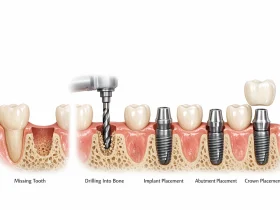

مراحل انجام بریج دندان

انجام بریج دندان معمولاً در چند مرحله و طی چند جلسه انجام میشود. ابتدا دندانپزشک وضعیت دهان و دندانها را بررسی میکند تا مطمئن شود دندانهای پایه توانایی نگهداری بریج را دارند.

در مرحله بعد دندانهای مجاور فضای خالی آمادهسازی میشوند. این آمادهسازی معمولاً شامل تراش دادن سطح دندانها برای قرار گرفتن روکش است. سپس از دندانها قالبگیری انجام میشود تا بریج در لابراتوار ساخته شود.

در برخی موارد تا زمان آماده شدن بریج اصلی، یک بریج موقت در دهان قرار داده میشود. پس از آماده شدن بریج نهایی، دندانپزشک آن را روی دندانهای پایه قرار داده و با استفاده از مواد مخصوص در جای خود ثابت میکند.